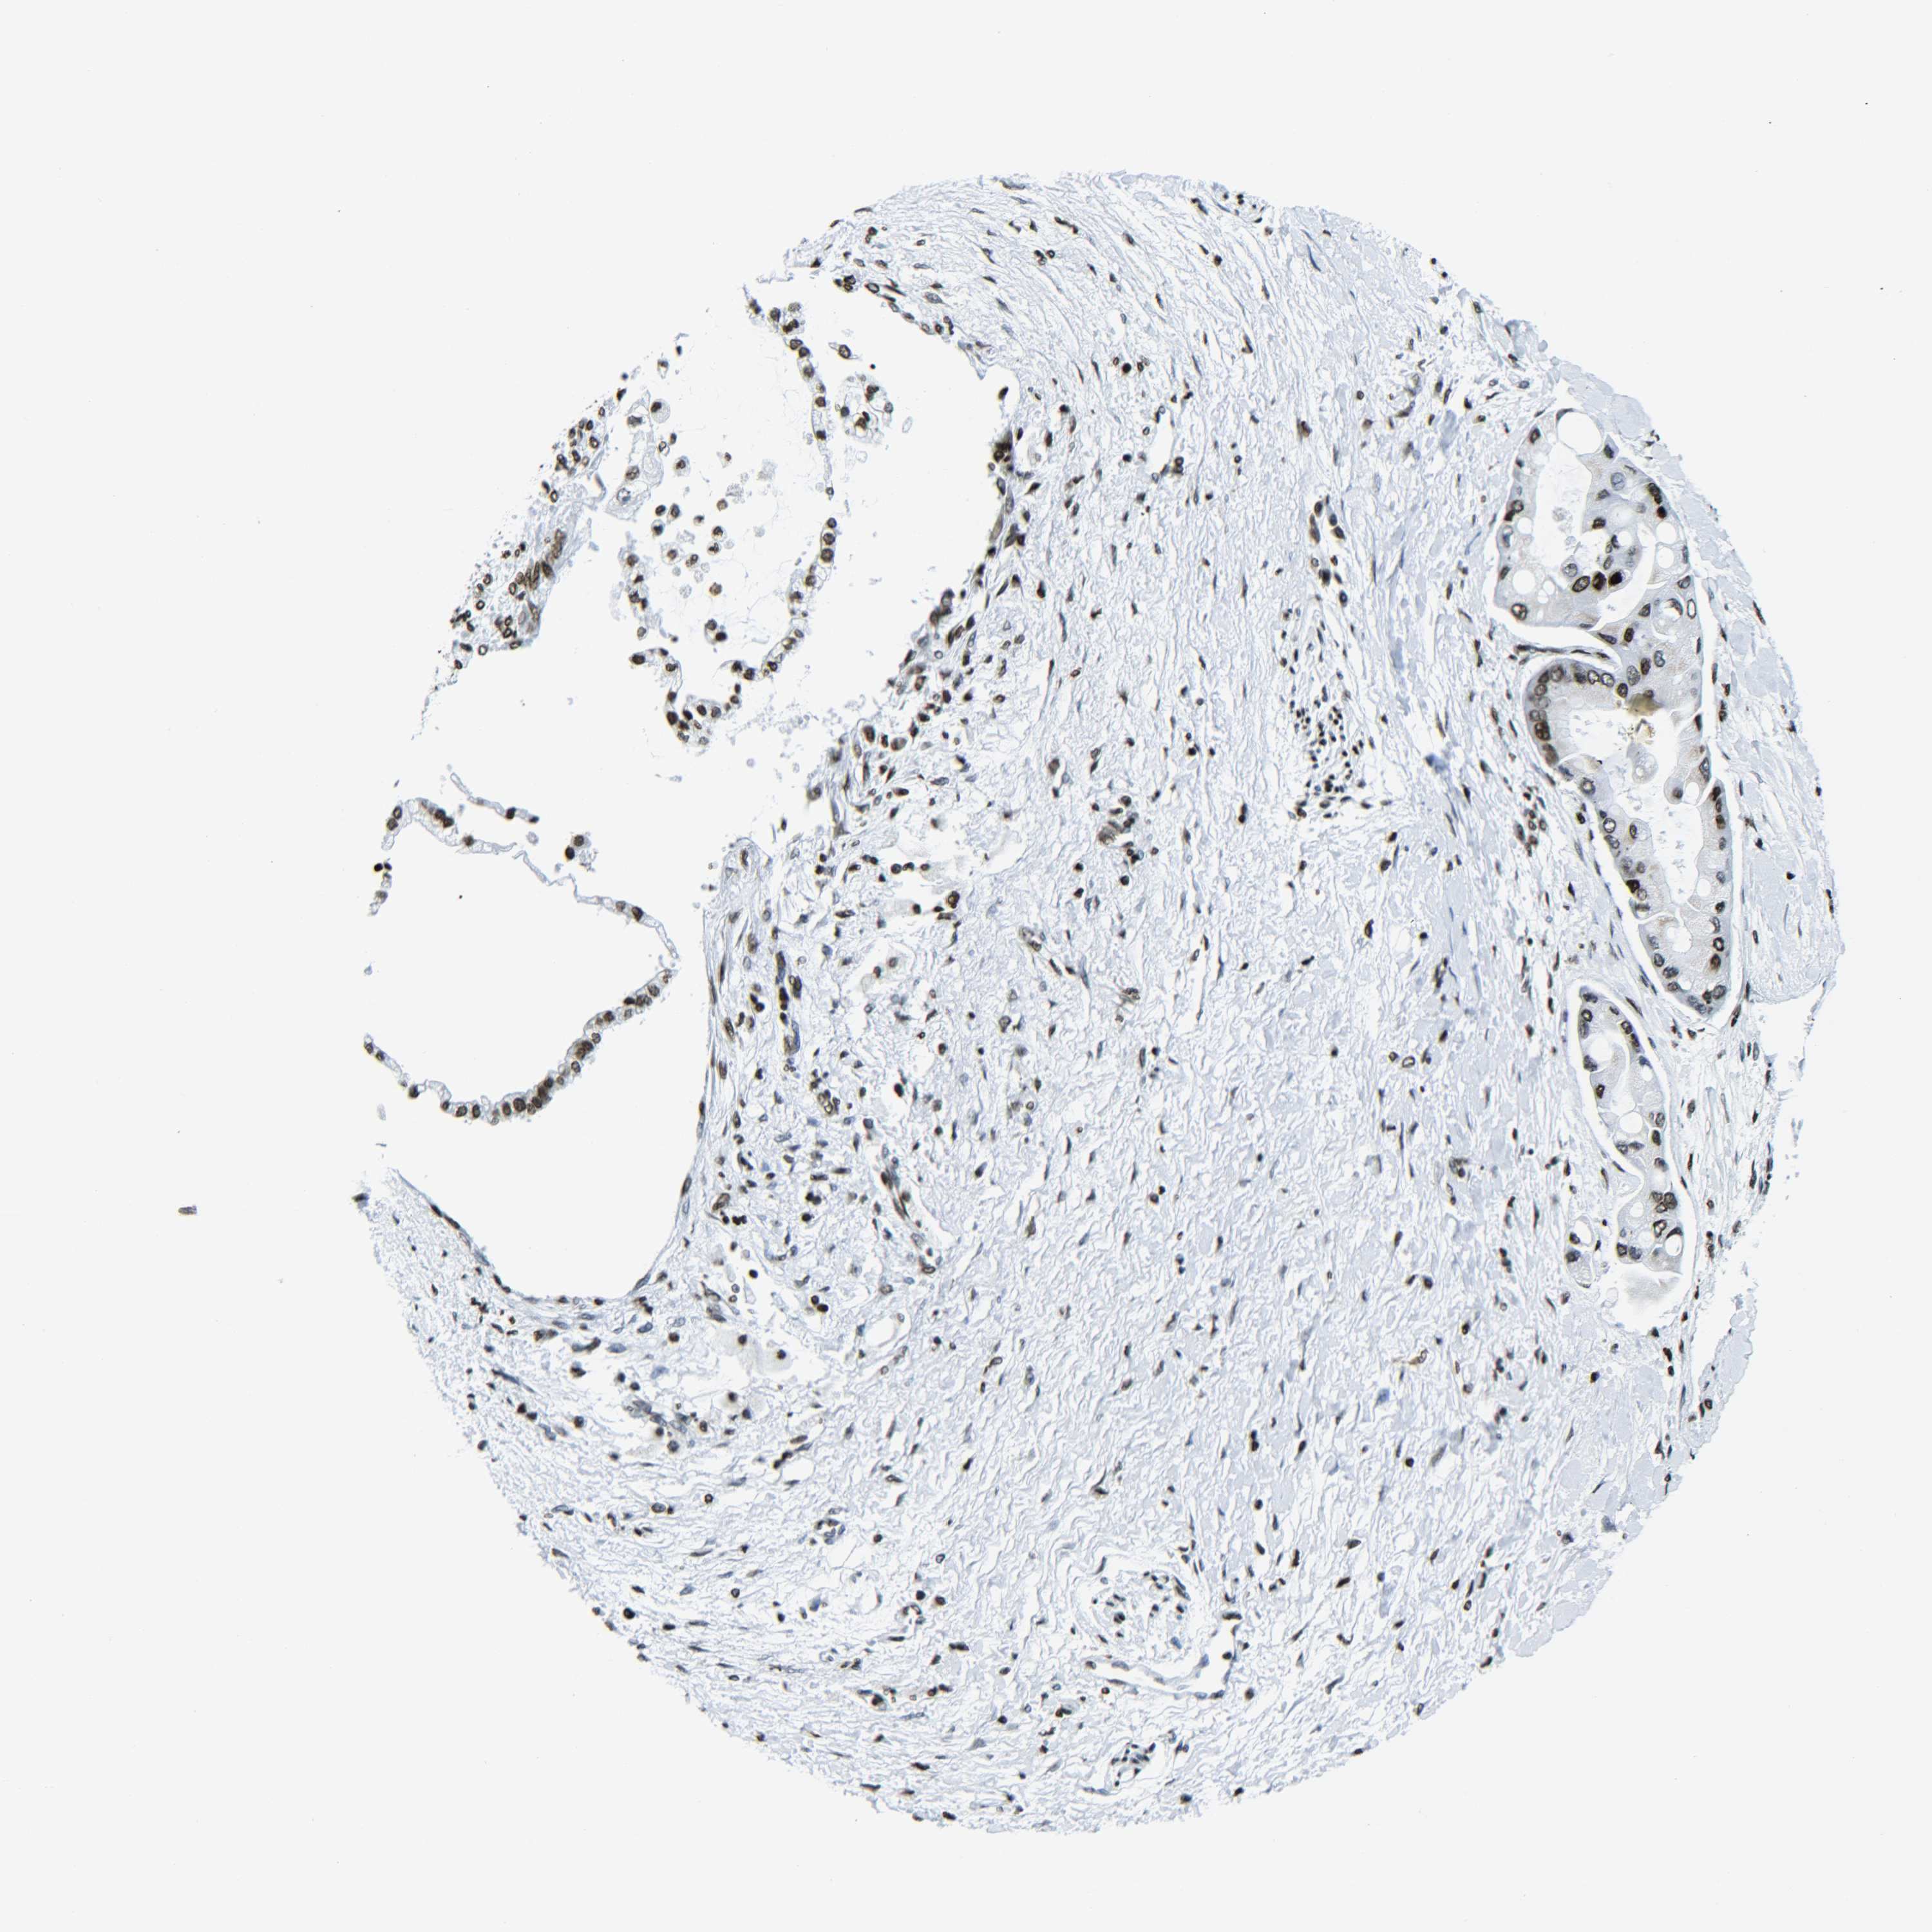

LIVER CANCER - Protein expressioni

A mouse-over function shows sample information and annotation data. Click on an image to view it in a full screen mode. Samples can be filtered based on level of antibody staining by selecting one or several of the following categories: high, medium, low and not detected. The assay and annotation is described here.

Note that samples used for immunohistochemistry by the Human Protein Atlas do not correspond to samples in the TCGA dataset.

Antibody stainingi

Antibody staining in the annotated cell types in the current human tissue is reported as not detected, low, medium, or high, based on conventional immunohistochemistry profiling in selected tissues. This score is based on the combination of the staining intensity and fraction of stained cells.

Each image is clickable and will lead to virtual microscopy that enables deeper exploration of all samples and also displays staining intensity scores, fraction scores and subcellular localization as well as patient and tissue information for each sample.

Antibody HPA041189

Antibody HPA051647

Antibody CAB012264

Staining

High

Medium

Low

Not detected

Intensity

Strong

Moderate

Weak

Negative

Quantity

>75%

75%-25%

<25%

None

Location

Nuclear

Cytoplasmic/membranous

Cytoplasmic/membranous,nuclear

Cholangiocarcinoma

Carcinoma, Hepatocellular, NOS